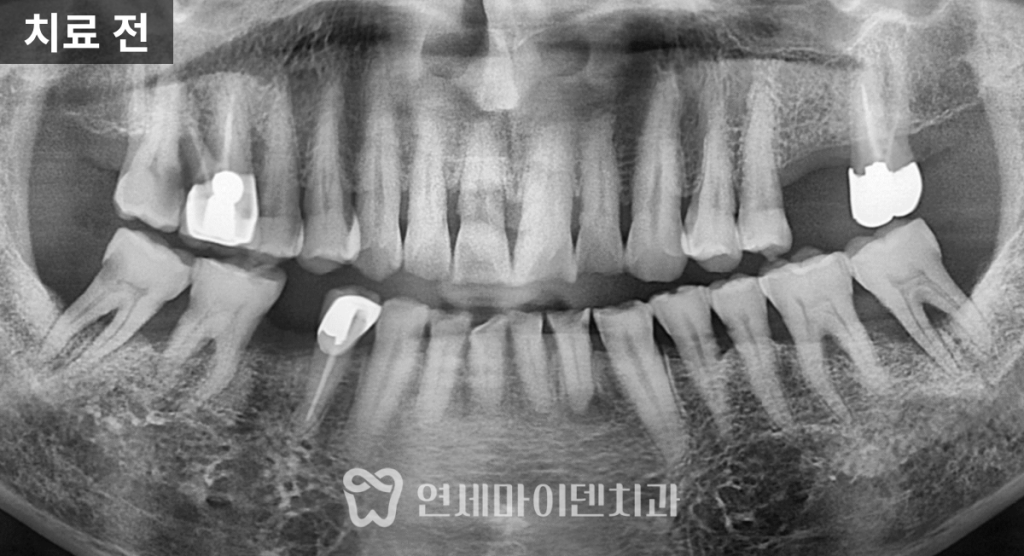

70대 고령 환자의 건강보험 임플란트 케이스입니다.70대 고령 환자 임플란트 진단

이번 케이스는 70대 환자분으로,

어금니 두 개에 임플란트 치료가

필요한 상황이었습니다.하지만 임플란트 치료는

결손 부위만 보고 바로 수술을 결정해서는 안 됩니다.어금니와 앞니 주변의 잇몸 상태,

충치 유무,

그리고 전체적인 교합 관계는

임플란트의 장기적인 안정성과

직결되기 때문입니다.

이번 사례에서도

임플란트가 필요한 부위 외에

다른 치아에서

잇몸 질환과 충치가 함께 발견되었습니다.따라서 이번 치료는

오랫동안 건강하게 유지될 수 있습니다.3D 가이드 임플란트 계획

임플란트는

뼈와 잇몸의 상태를 고려해

정밀하게 설계되어야 하는 치료입니다.

수술 전 3D CT 촬영을 통해

임플란트 식립 위치와 각도를

미리 계획했고,

주변 해부학적 구조물을 피하면서

안정적인 식립이 가능하도록 준비했습니다.

또한 염증 발생 가능성을 낮추기 위해

이번 케이스에서도

임플란트 픽스처를

뼈 레벨보다 약간 안쪽으로 식립해

안정성을 높였습니다.건강보험 임플란트 최종 보철